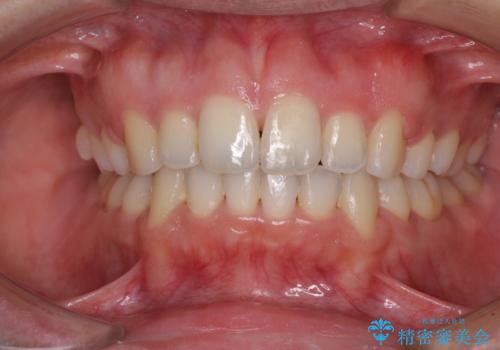

掃除しにくい前歯と閉じにくい口元 目立たないワイヤー装置での抜歯矯正